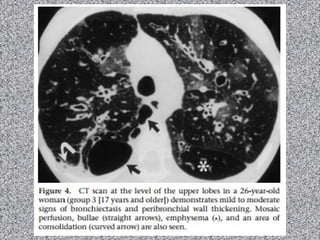

Fibrose cística: imagem

TACR de tórax:

Bronquiectasias (principal achado):

Pode ser dos 3 tipos; geralmente bilaterais;

Predomina nos lobos superiores;

Espessamento brônquico;

Impactação mucoide pode ocorrer;

Nódulos centrolobulares;

Árvore em brotamento;

Consolidações;

Lesões císticas ou bolhosas nos ápices;

Linfonodomegalias hilar e mediastinal

Anormalidades pleurais (derrame e/ou espessamento)

Fibrose Cística

Homem de 37 anos com tosse crônica e dispneia progressiva